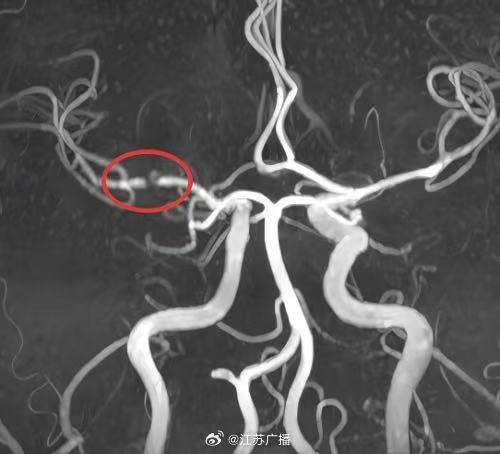

小潘今年29岁,平时饮食不节制且缺乏运动,还有吸烟的习惯,体重达到了115公斤。最近,他在早晨起床时突然感到头痛、视物模糊和口角歪斜。经过医院检查后发现,他患上了多发急性脑梗死

29岁230斤小伙一觉醒来突发脑梗肥胖与不良习惯埋下隐患!小潘今年29岁,平时饮食不节制且缺乏运动,还有吸烟的习惯,体重达到了115公斤。最近,他在早晨起床时突然感到头痛、视物模糊和口角歪斜。经过医院检查后发现,他患上了多发急性脑梗死。

长期肥胖、高血压以及吸烟导致了小潘脑血管动脉硬化和狭窄,而夜间严重的睡眠呼吸暂停和低氧血症缺氧进一步诱发了他的脑血管疾病。